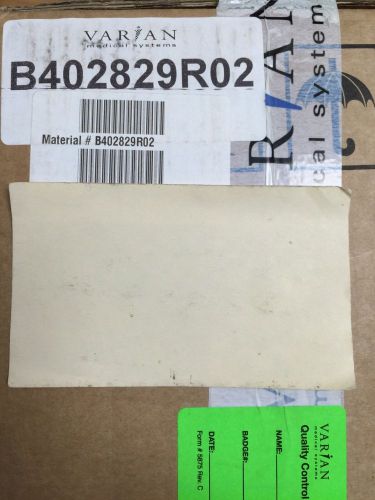

Varian Medical Systems OBI Motor Driver PCB NEW